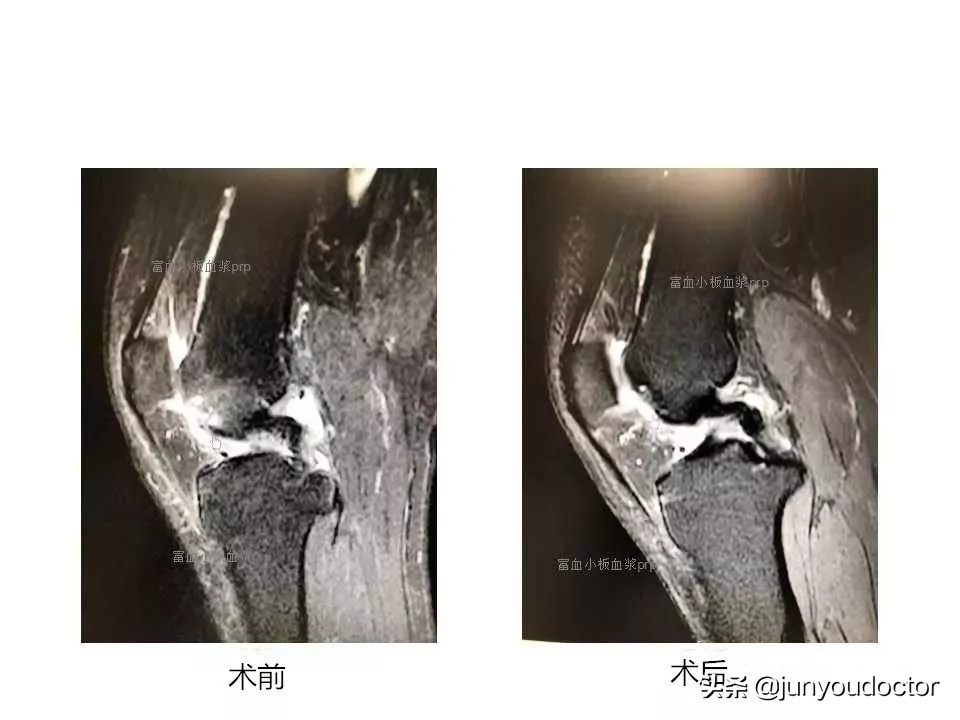

PRP案例展示

患者,女性,57岁,因膝关节滑车局部软骨损伤接受微创手术+PRP治疗,效果明确,见下方复查结果。